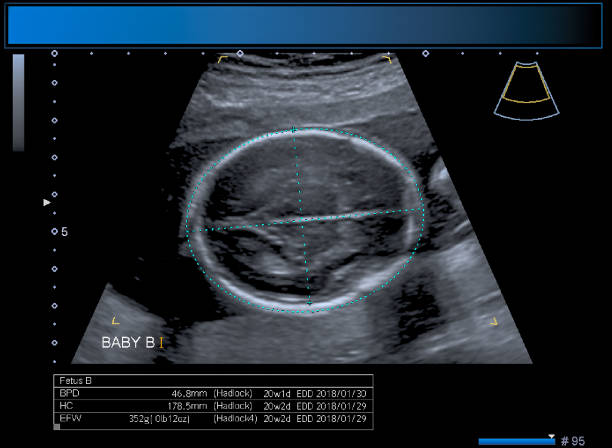

A tiffa scan in pregnancy—Targeted Imaging for Fetal Anomalies scan—is generally performed between the 18th and 22nd weeks. At this stage of pregnancy, the fetus has developed most of its important organs, and thus it would be the ideal time to assess physical structures and detect any abnormalities. At Dr. Aravind's IVF, the very best radiology team uses advanced ultrasound equipment so that even a clearer and more comprehensive image of the fetus is made available. This allows specialists to assess the baby's brain, heart, kidneys, spine, limbs, and other vital structures with utmost precision.

All steps of the tiffa scan procedure have been made safe, comfortable, and reassuring for every expected mother at Dr. Aravind's IVF. The whole scan usually lasts anywhere between 30 minutes to 45 minutes. During the scan, a trained sonologist slides a transducer over the patient's abdomen, taking high-resolution images of the fetus. Special preparation is not required from the mothers, but they might get a recommendation to keep their bladder moderately full for improved imaging. The Dr. Aravind's IVF team of experts details every step of the procedure, ensuring patients are calm and informed throughout the session.

In addition to performing routine imaging, the tiffa scan gives a detailed overview of overall well-being; it works great at detecting structural abnormalities, measuring fetal growth, examining placental position, and assessing amniotic fluid levels. At Dr. Aravind's IVF, should any developmental issues show up, doctors will use TIFFA results to work out an appropriate course of prenatal care. This method of early detection has assisted an innumerable amount of parents in taking steps toward a healthy result from a pregnancy. The scan will also highlight if it is a case of multiples and reverse twin growth if the pregnancy is of twins.